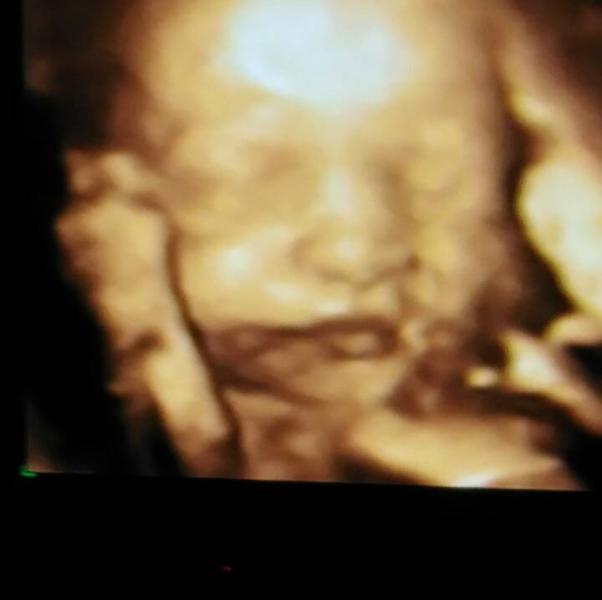

my sweet, sweet girl❤😍 oh how im so in love already!